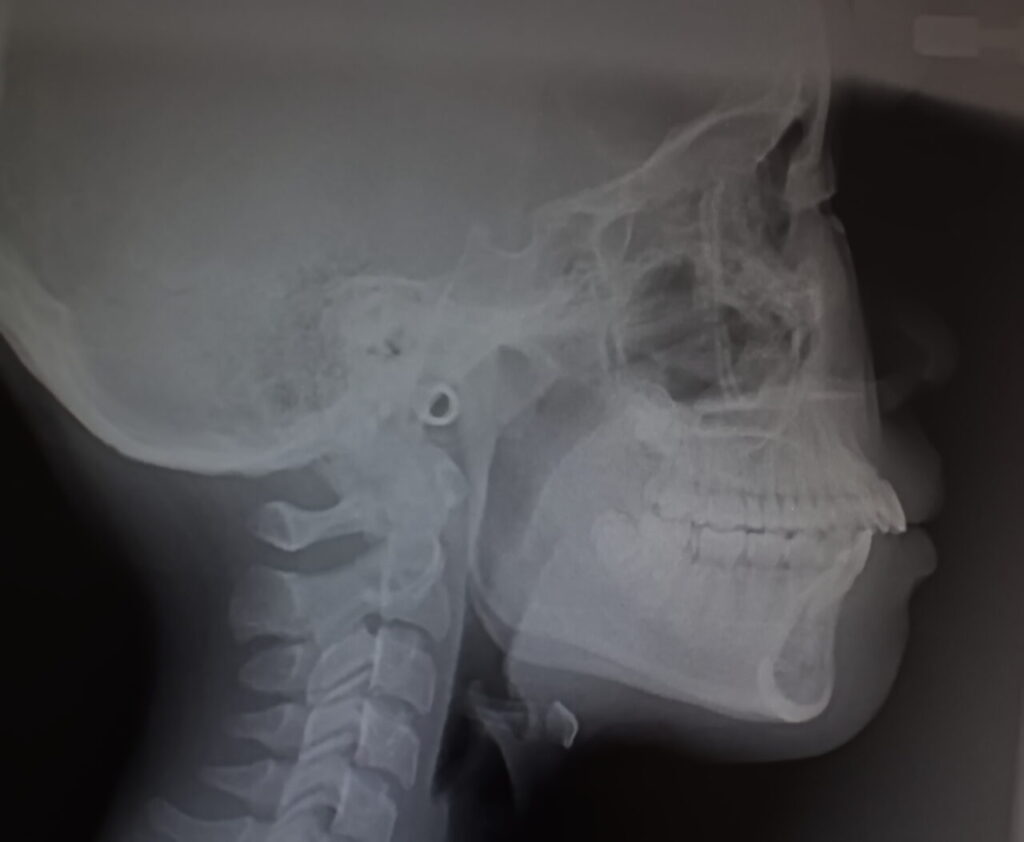

セファロ分析とは?

横顔のレントゲン(セファロ)を用いて、骨格の角度・歯の傾き・上下顎の位置関係などを数値化しながら分析する検査。

ガミースマイルに関連する、

・上顎骨の長さ

・上下のあごのバランス

・口元の突出度

などを精密に評価できます。

骨格原因が疑われる場合、この分析が治療方針の基盤になります。

矯正治療が必要か、外科手術が必要か、その判断ができるのは セファロがある医院だけです。